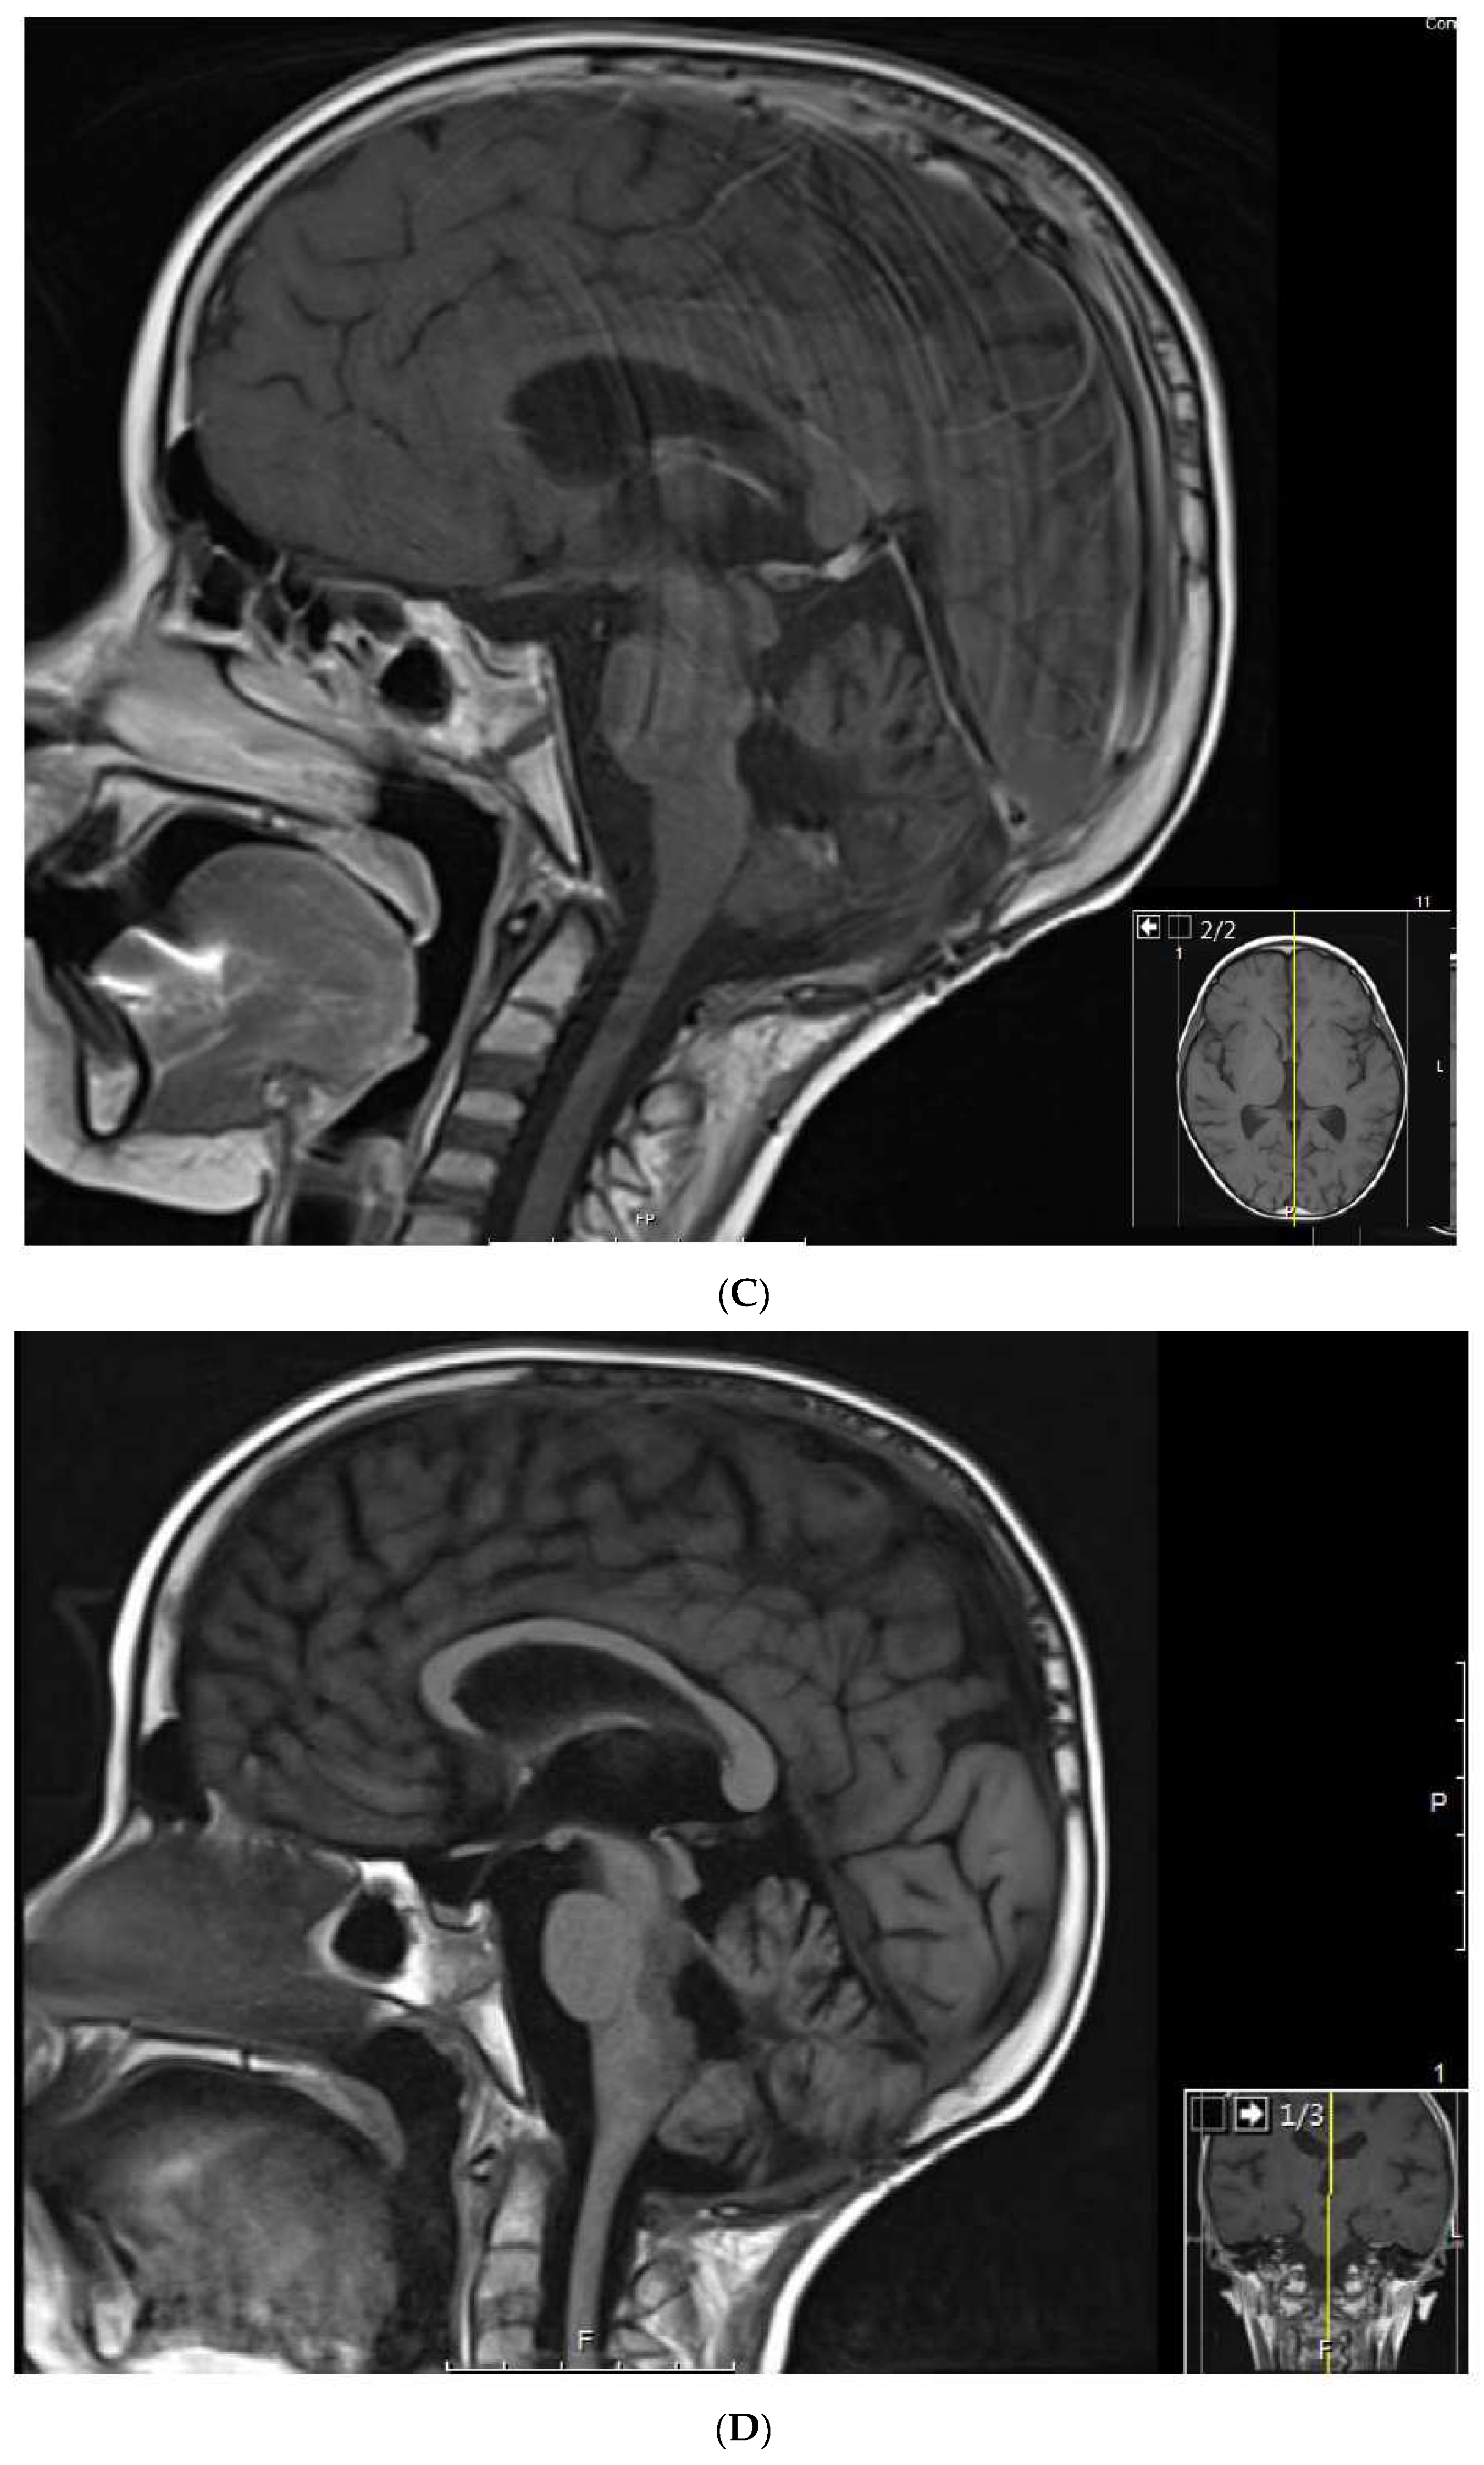

1.6. Patient 6

This patient is a Hispanic girl found to have a large cervicomedullary tumor with a cervico-thoracic central syrinx with tumor seeding when she presented with right shoulder drop and right upper-extremity weakness at 3 years of age (Figure 4A). She had resection of the cervicomedullary portion of the tumor. Evaluation revealed a type 2 neurocytoma of the spine.

Figure 4.

Patient 6: (A) MRI shows a 4.5 cm homogeneously enhancing expansile intramedullary tumor involving the medulla and upper cervical cord down to the level of C3–C4 (arrow) with an elongated syrinx extending inferiorly to the T3–T4 level; (B) the tumor was removed and treated with radiation but came back, for which it was treated with nine cycles of topotecan–ifosfamide–carboplatin with no significant change in tumor size (arrow) but significant toxicity, for which treatment was changed to metronomic chemotherapy; (C) after 3 months on metronomic chemotherapy, the patient recovered from toxicity and the tumor was slightly decreased; (D) the tumor was stable at the end of 4 years of metronomic chemotherapy.

She subsequently received intensity-modulated radiotherapy to the tumor bed and residual cervico-thoracic tumor. Following radiation, a residual 11 mm expansile cervicomedullary nodule, centered at the C3–C4 level, was documented. Five months later, she developed progressive disease with increased size of the cervicomedullary nodule to 15 mm and development of a new second focus of enhancement on the ventral aspect of the spinal cord at C2. She was treated with topotecan, ifosfamide and carboplatin (TIP). She had significant hematologic toxicity and infectious complications during this treatment and no change in tumor size after nine cycles (Figure 4B), for which she was changed to metronomic chemotherapy with 21 days of temozolomide (60 mg/m2 day) aleternating with 21 days of CTX (50 mg/m2), VA (15 mg/kg), celecoxib (250 mg/m2/day) and bevacizumab (5 mg/kg IV every 3 weeks). Tumor response was noted 3 months after treatment with decreased tumor size to 9–10 mm (Figure 4C). Tumor size remained stable on subsequent studies, and temozolomide and CTX were stopped at 18 months, celecoxib and VA were stopped at 36 months, and bevacizumab was stopped at 48 months (Figure 4D). Metronomic chemotherapy was restarted after tumor progression was documented 10 months later (Table 1). She developed stable disease and treatment was stopped 15 months later. She remains with stable disease 4 years off therapy.